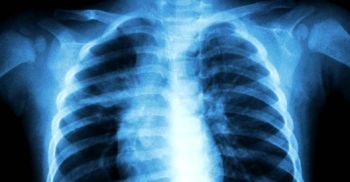

‘วัณโรค’ เป็นแล้วไม่เท่ากับตาย หากรักษาทันท่วงที

8 เม.ย. 2563